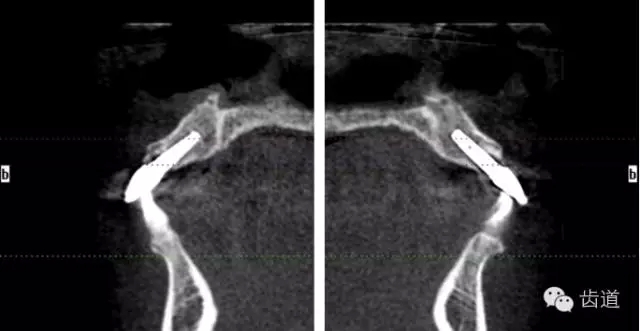

術(shù)后CT

戴牙后CT